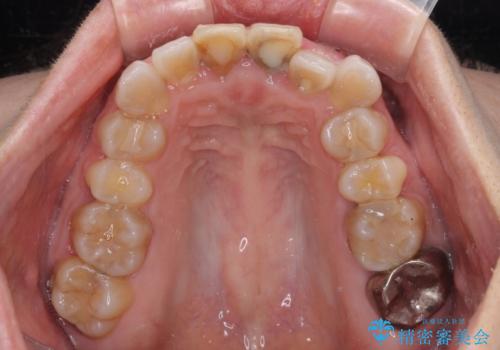

- 変色した前歯2本を気にして来院された患者様です。

右側の前歯は根管治療を行い、その後2本とも歯質に近い素材の土台を植立してオールセラミッククラウンにて補綴することとしました。